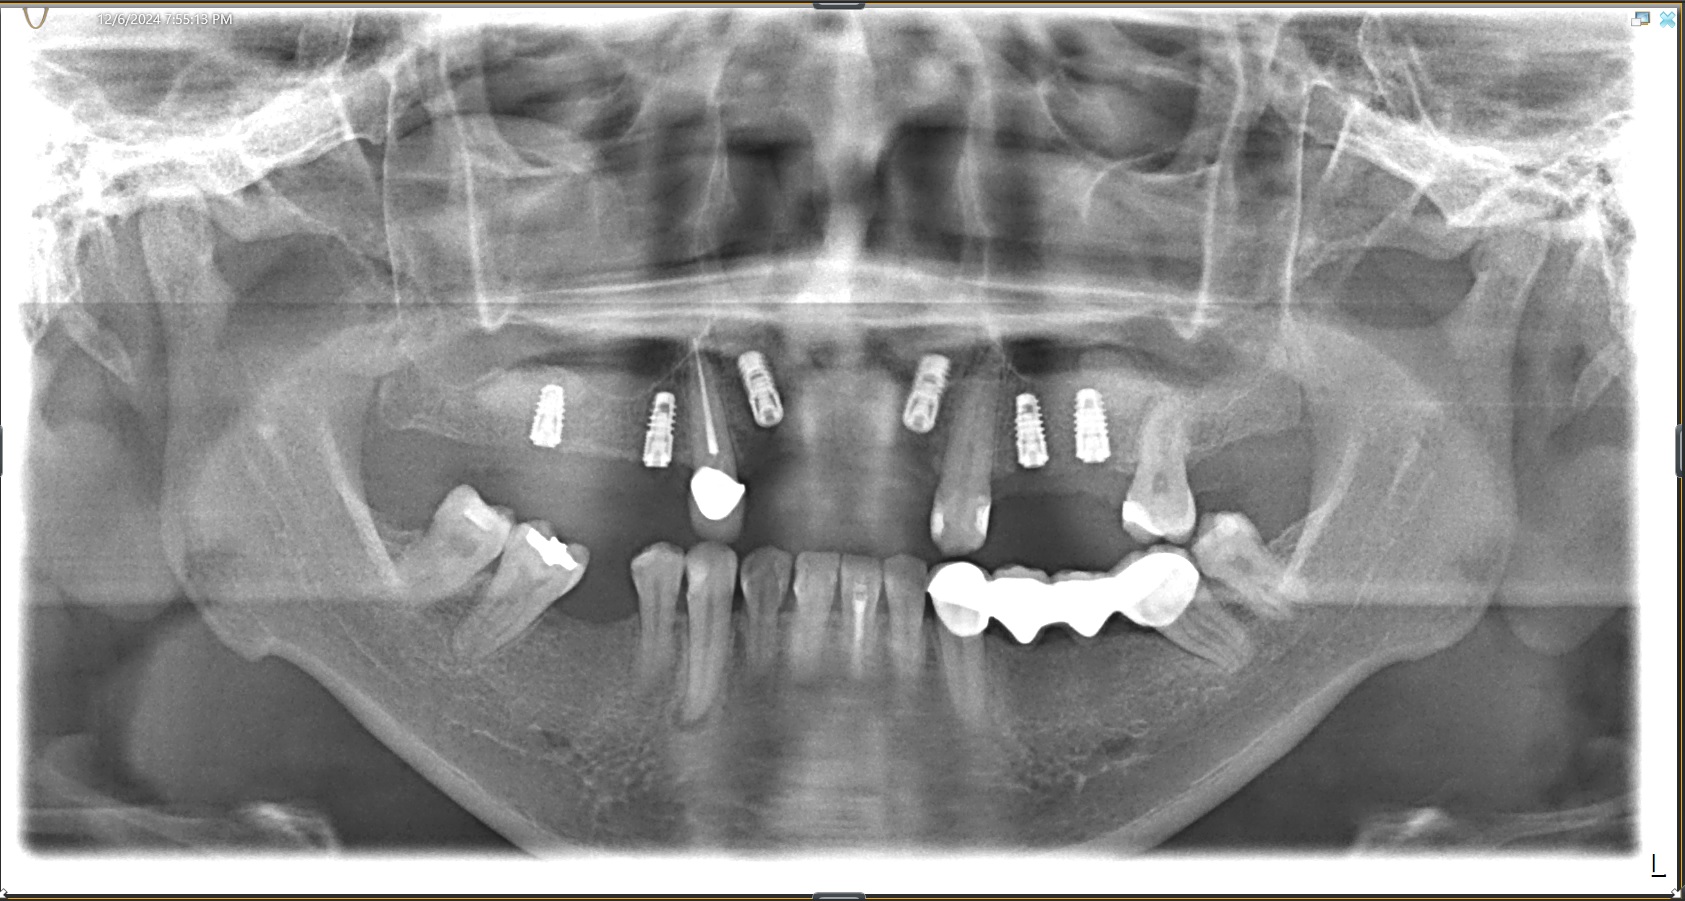

Edit Record Check our patient data records. Add patient information Patient Info Profile picture Last Name First Name Middle Name Birthdate Age Street Barangay City Country Zip Code Contact number Email Procedure 04/09/24 fiber post 3.500 x 2 core build up alumina crown 04/13/24 Balance paid for crown-10,000 LC #23 cervical,mesial,distal 06/01/24 Odontectomy Upper canine(extra tooth) area;maxillary near nasopalative nerve **GBR-stickbone + PRF membrane **R&L upper sinus lift left sinus lift- Bio oSS collagen(13x25 mm) **bone graft material (20 gram=4cm (Bio Oss 0.25m-1mm **sinus lift ( area of 26 to 16) w/GBR red tubes-12 tubes yellow tube-2 tubes nylon4/0-(x3) monofilament nylon 06/08/24 check up 06/14/24 suture removal LC #41 M,D #42 M,D #32 M,D #43 M xray 06/21/24 adjustment of Dentures 07/20/24 Recall and xray 12/06/24 **bone graft material (0.5 gram=1cm) (Bio Oss 0.25m-1mm) **Implant 3(FIS) 3(FIT) #14-FIS 3.8x8.5mm #12-FIS 3.8x10mm #22-FIS 3.8x10mm #16-FIT 4.3x7mm #25-FIT 4.3x8.5mm #26-FIT 4.8x8.5mm 12/18/24 suture removal ozone 03/22/25 Healing abutment #22 FIS 4mm #12 FIS 6mm #14 FIS 2mm #26 FIT 4mm #25 FIT 3mm #16 FIT 3mm 04/09/25 healing abutment temporary denture 05/01/25 3D scanning shade: A3.5 cervical, A3 body full contour zirconia top abutment provided top abutment #12 O/D: 5MM, G/H: 5MM, A/H: 8MM #14 O/D: 4.5, G/H: 2MM, A/H: 6MM #16 O/D: 4.5MM, G/H: 5MM, A/H: 6MM #22 O/D: 5MM, G/H: 4MM, A/H: 8MM #25 O/D: 4.5, G/H: 4MM. A/H: 4MM #26 O/D: 4.5, G/H: 5MM, A/H: 6MM 05/16/25 Installation of porcelain 11-12-21-22, 24-25-26 14-15-16 no porcelain crown OP biogaia paid 05/24/25 #38 Biomemetics w/ fiber CaoH 06/04/25 LC #28 (O,lingual pit) 06/18/25 LC #48 (O,M) CaoH 09/13/25 Op for implant recall for 3months 10/17/25 4 units of alumina crown #33, 34, 35, 36 shade - A3.5 cervical, A3 body scanning DP - 29,000 10/23/25 installation of 4 units alumina crown #33, 34, 35, 36 02/21/26 OP air poolish File img_1712655813987.jpg File 2 img_1712655921022.jpg File 3 ms-_vasquez.docx File 4 img_20241206_170340_537.jpg File 5 1000002173.jpg File 6 img_20241206_180509_305.jpg File 7 img_7756.jpeg File 8 marla_vasquez_120624.jpg File 9 File 10 File 11 File 12 File 13 File 14 File 15 File 16 File 17 File 18 File 19 File 20 Retain Record Retain Record Yes No Save Your Changes